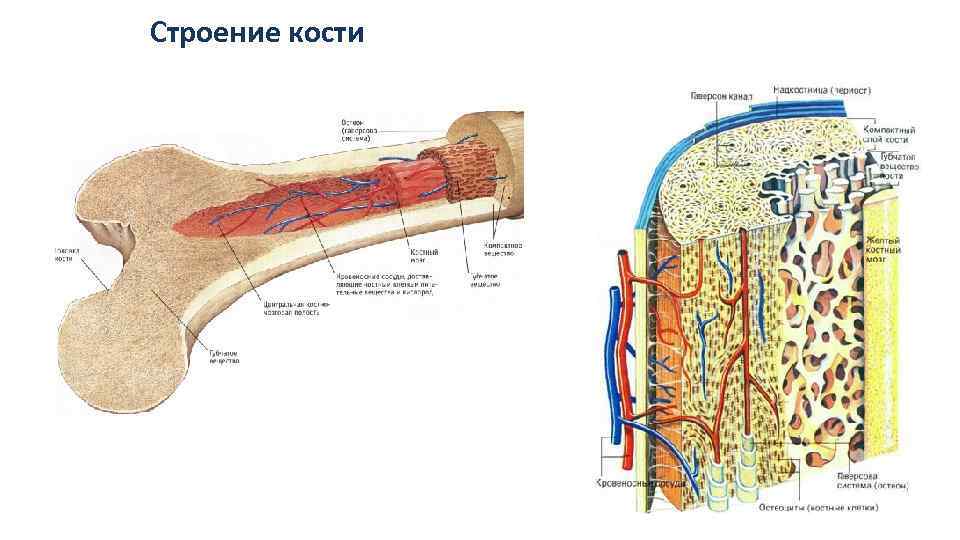

Изучение костного мозга: анатомия и функции